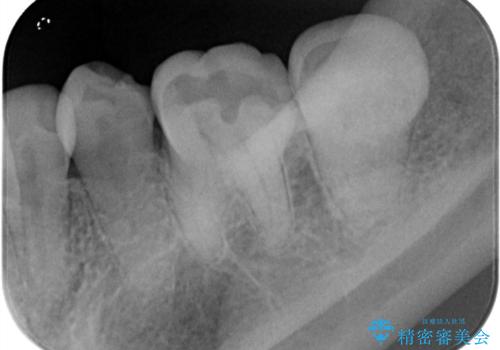

樋状根(といじょうこん)の根管治療

- 昨夜から、寝れないぐらいズキズキ痛む歯があることを主訴に来院されました。

歯髄診にて患歯を特定し、不可逆性歯髄炎の診断のもと治療を行っています。

治療中には過去に修復された材料の下に虫歯を認めましたが、破折線はみとめられませんでした。

治療後すぐに症状は改善され、今後クラウン修復を行う予定です。